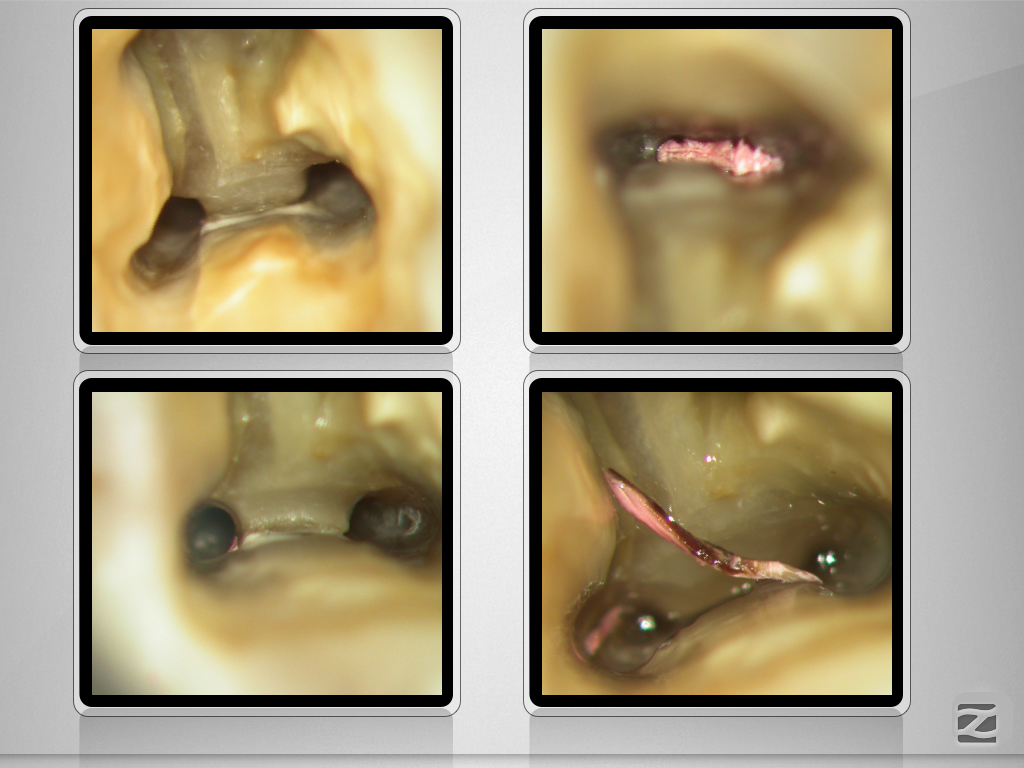

37D.012

Ausgedehnte apikale Lyse